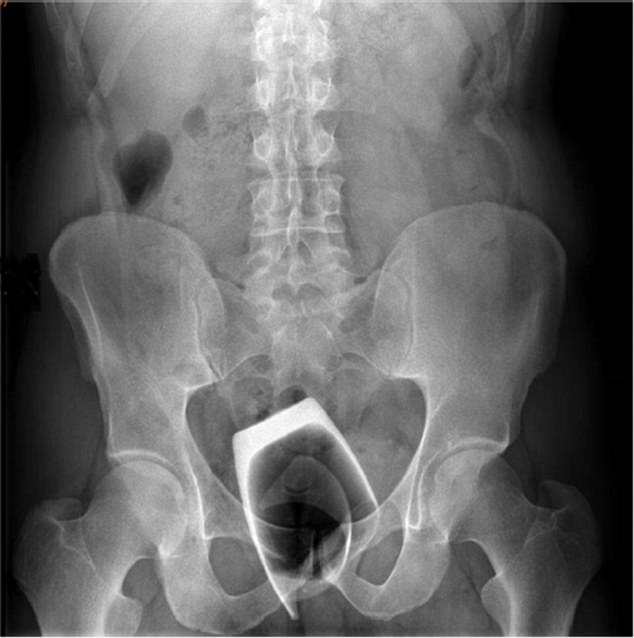

Một người đàn ông cố tình nhét một cái cốc uống rượu thay vì dùng đồ chơi người lớn vào hậu môn để tăng cảm giác tình dục.

Nam bệnh nhân thú nhận với bác sĩ rằng đã đẩy vật thể này vào từ phía hậu môn để tăng "kích thích tình dục". Khi ông ta cố gắng lấy cái cốc ra, nó đã bị vỡ thành từng mảnh khiến thủy tinh găm vào da thịt gây chảy máu.

Ông không cảm thấy đau đớn song 2 ngày sau phải đến bác sĩ để được tư vấn vì cảm thấy lo lắng về sức khỏe. Kết quả chụp X-quang cho thấy các mảnh thủy tinh trong trực tràng bệnh nhân. Các bác sĩ phải mổ mở rộng trực tràng bệnh nhân để đưa thiết bị vào kiểm tra. Các mảnh vỡ sau đó đã được lấy ra.